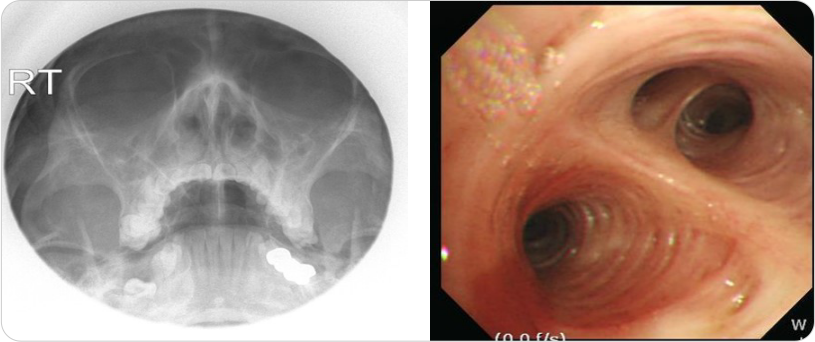

기관지확장증 진단을 위해 어떤 검사방법이 있는가요?

흉부 X선 검사 및 흉부 CT 검사에서는 폐의 침윤 소견 및 폐의 낭성 변화로 인한 기찻길 모양의 tram track sign 및

반지 모양의 signet ring sign을 확인할수 있습니다.

한편 동반되는 부비동염을 확인하기 위하여 부비동 X선 촬영을 하기도 하고, 동반되는 폐기능 감소를 확인하기 위해서

폐기능 검사를 시행하기도 하며, 감염 원인균 확인을 위해서 객담 배양 및 감수성 검사를 하고 객혈의 출혈 부위 확인을 위해서

기관지 내시경을 시행하기도 하며, 동반 질환의 진단을 위해서 혈액 검사 및 알러지 검사를 하기도 합니다.

img

그림3 : 기관지확장증의 부비동사진(양쪽 부비동염) 및 기관지내시경 사진(기관 내 염증 및 출현흔 확인)